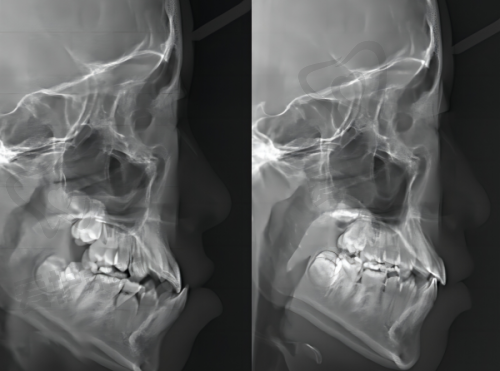

张婕妤医生从事口腔正畸临床工作十余年,曾就职于天津口腔医院,从医严谨,审美水平较高。擅长时代天使隐形矫正、隐适美隐形矫正、金属托槽矫正、儿童及青少年早期矫正等。她是中华口腔医学正畸协会会员、美国隐适美隐形矫正认证医生、时代天使隐形矫正认证医生,能为患者提供专精的正畸方案。

天津诺尔口腔医院非常注重设备技术的引进和更新。医院引进了精良的口腔医疗设备和技术,为诊断和治疗提供了有力支持。在种植方面,引入了智能化种植导航系统。有患者分享,医生用导航系统提前规划种植角度,全程几乎没肿痛,短时间内就能正常吃饭,大大提高了种植牙手术的精细度和舒适度。在矫正方面,采用 3D 扫描矫正技术,通过三维建模预览结果,能避免“钢牙妹”时期的尴尬,特别适合职场人士。医院不断更新设备和技术,保持在口腔医疗领域的精良地位,为患者提供更优质的治疗体验。